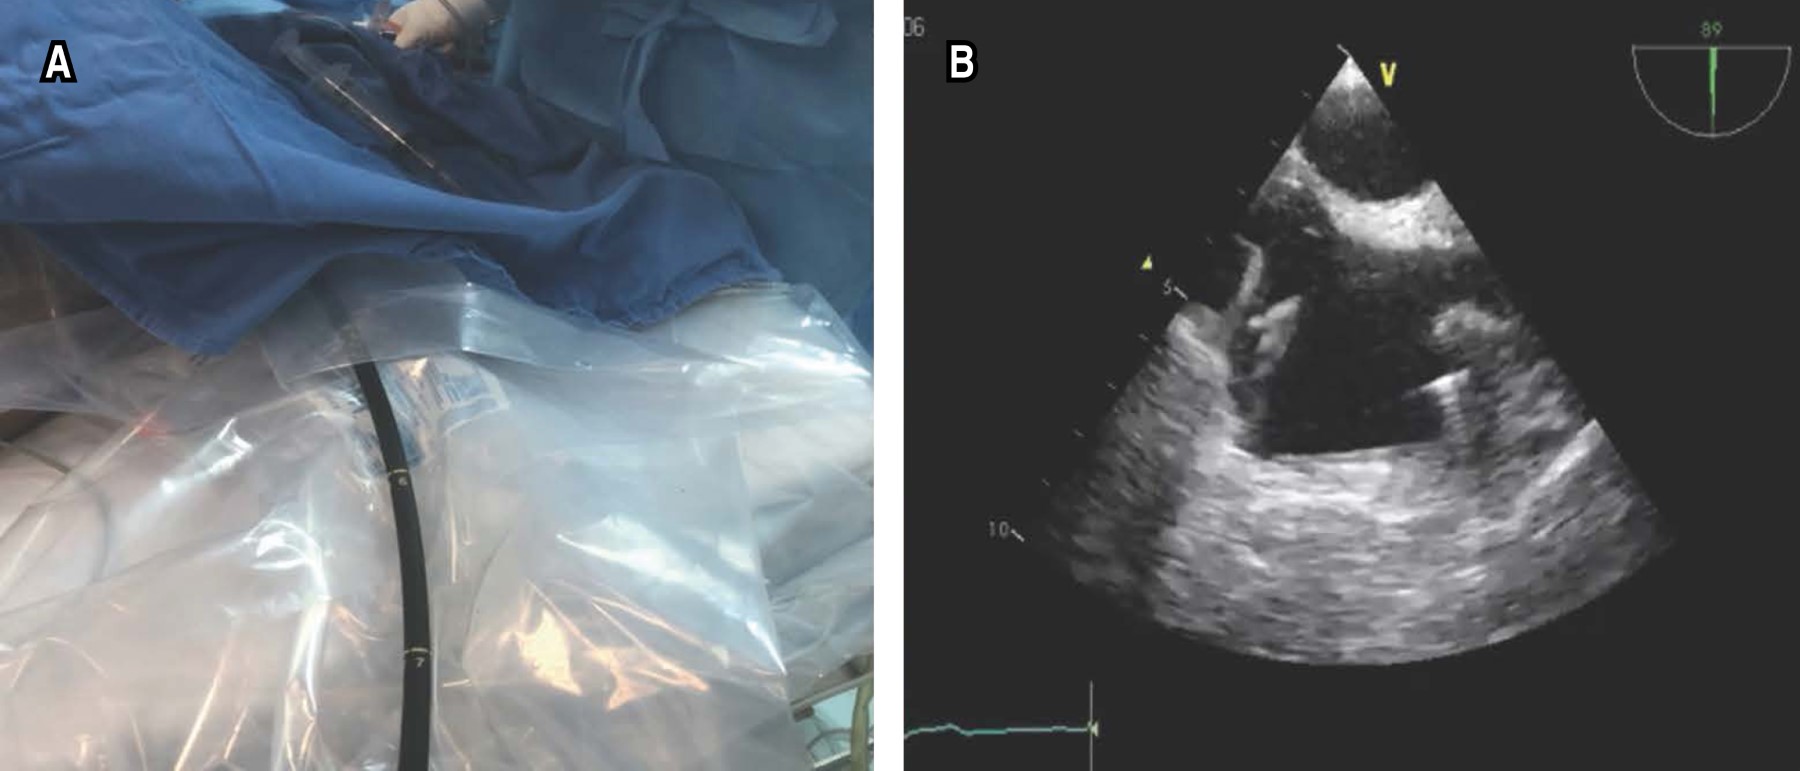

As the first step of the flowchart (Figure 1), all personnel must have adequate PPE and protect the TEE probe (Figure 2A). After intravenous sedation, the TEE probe is inserted, being the projection selected to guide the procedure the mid esophageal bicaval 90-110 degree view (Figure 2B), where we can guide in real time the correct positioning of the return (jugular) cannula (Figure 3A), which should be placed in the mid portion of the right atrium in the direction of the tricuspid valve. Adequate flow can be assessed by color Doppler (Figure 3B). The TEE probe with the same degree of angulation is advanced distally toward the esophagus to observe the inferior vena cava and the extraction cannula (femoral) which should be separated 8 to 10 cm from the return cannula (Figure 3C and D); this limits suction and recirculation phenomena.